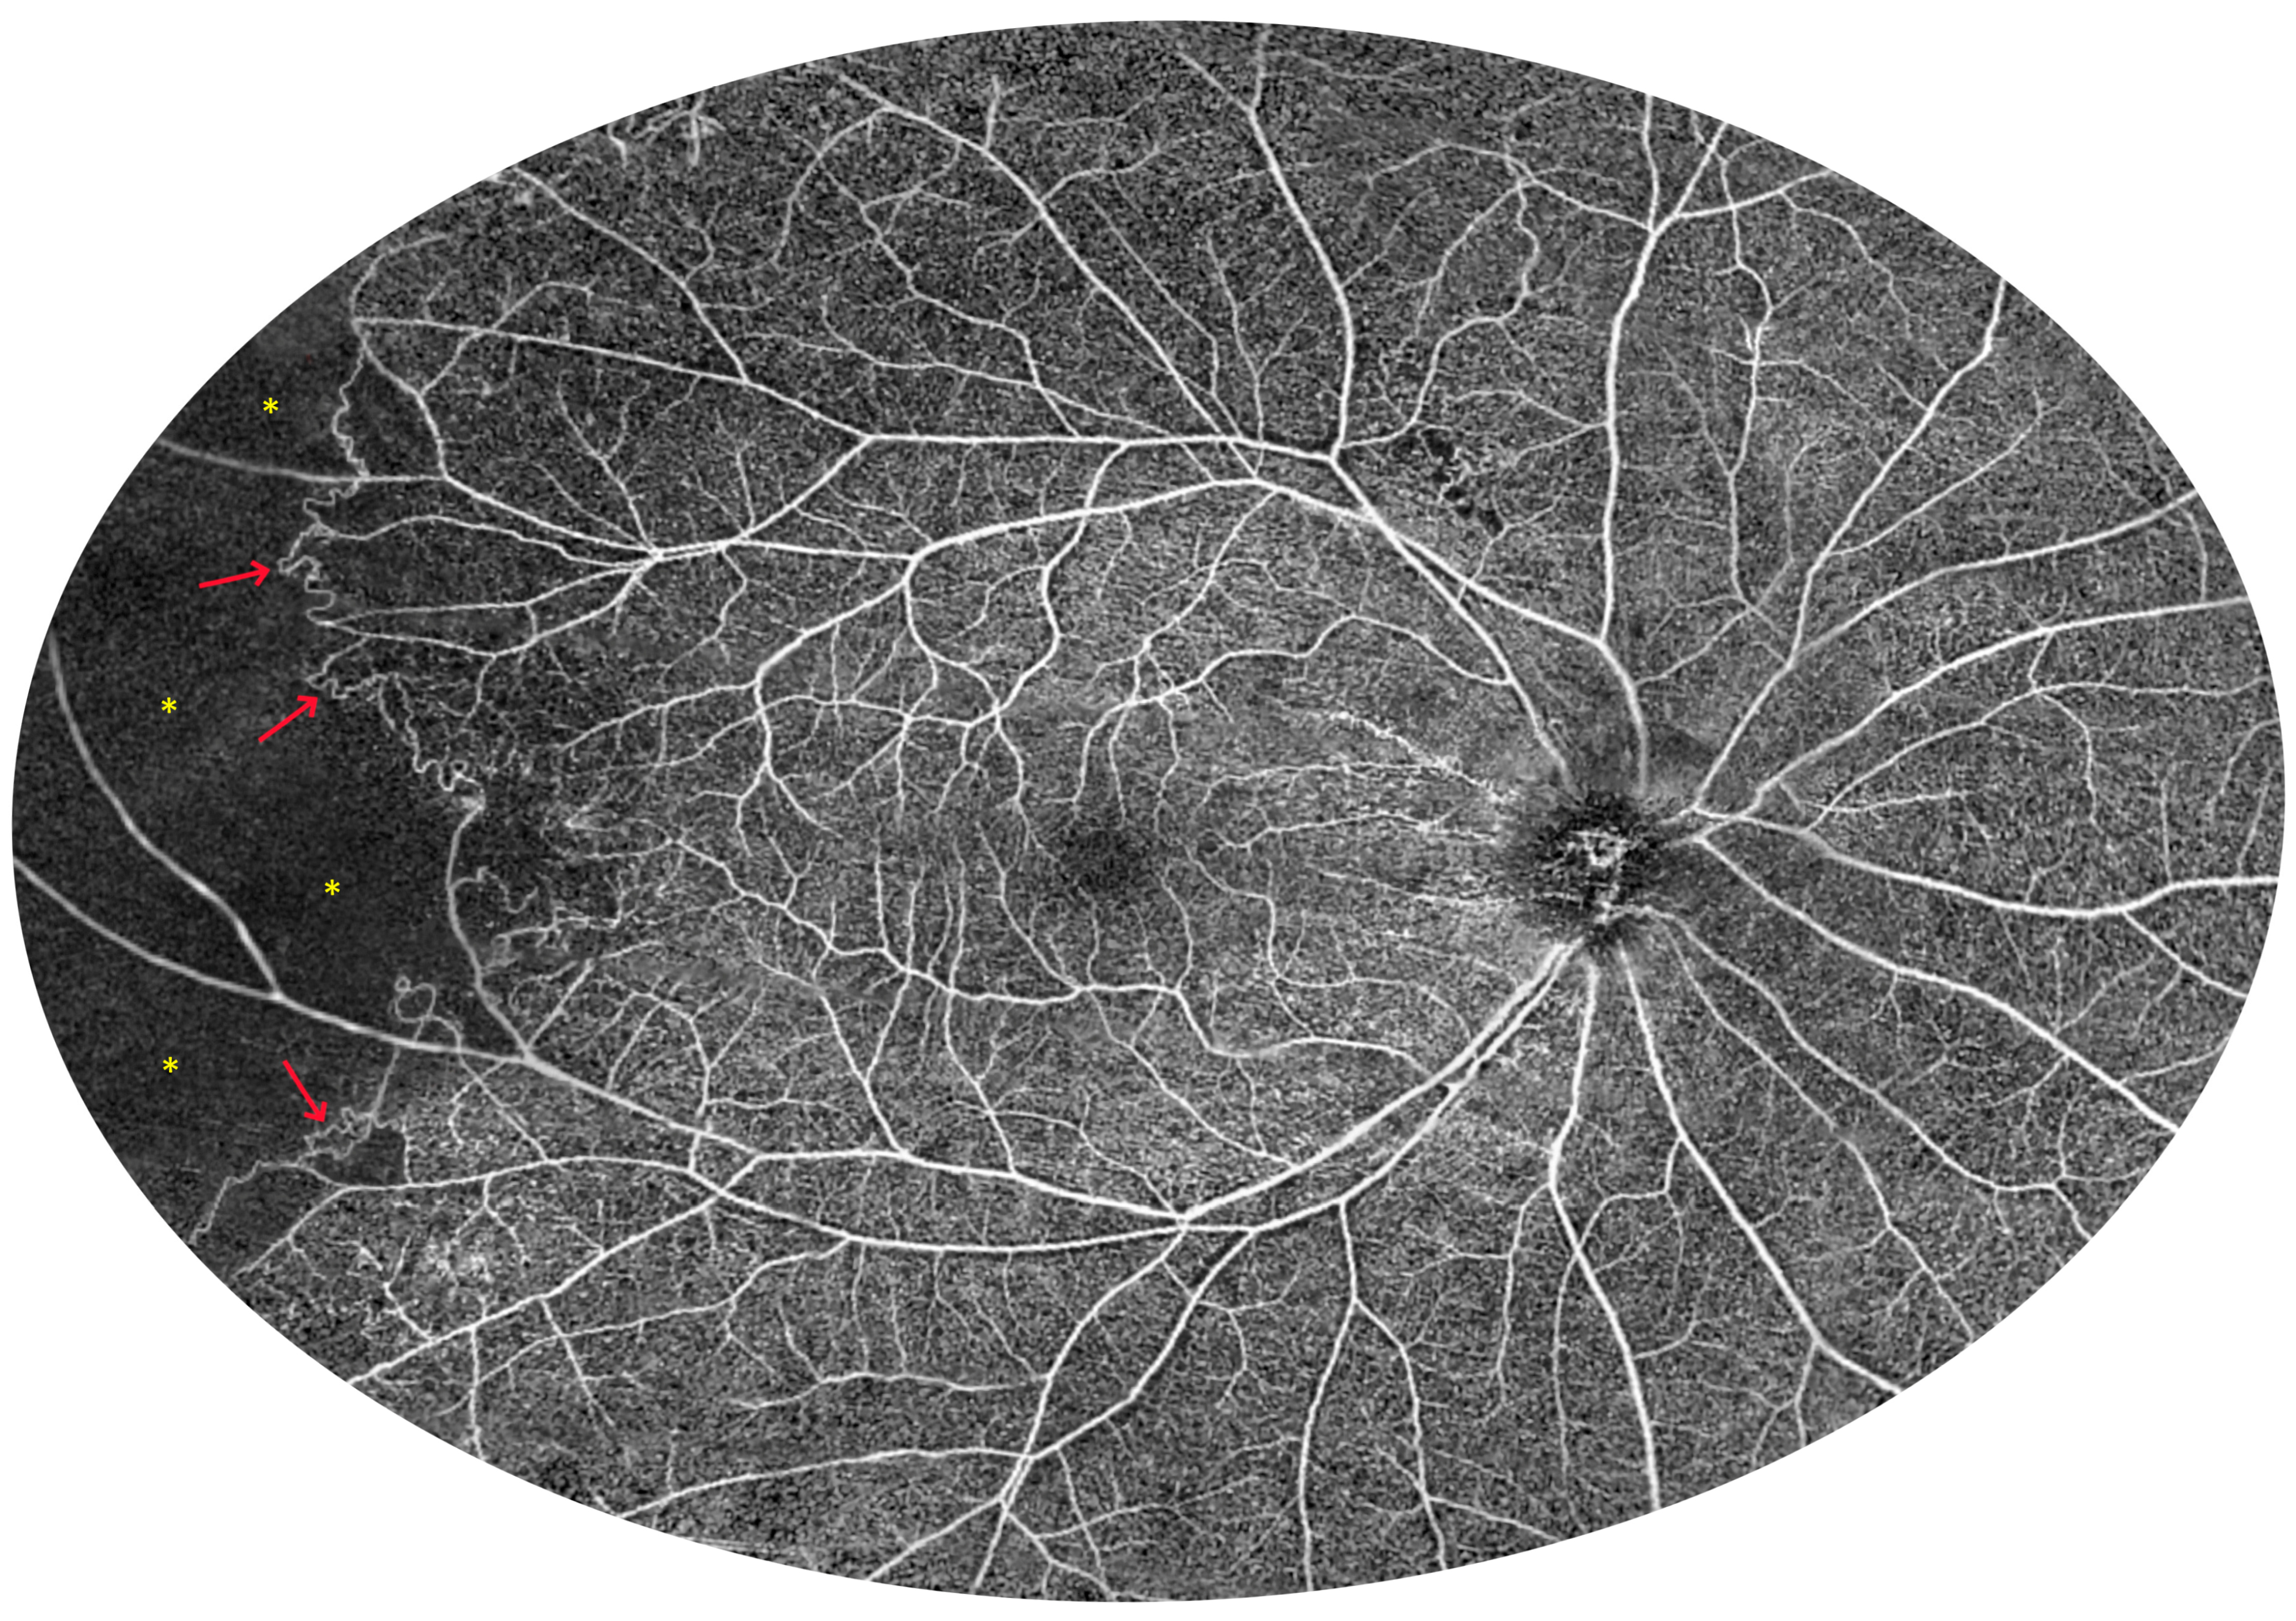

3.2. Angio-OCT Measurements

3.4. UWF Angio-OCT Mosaics